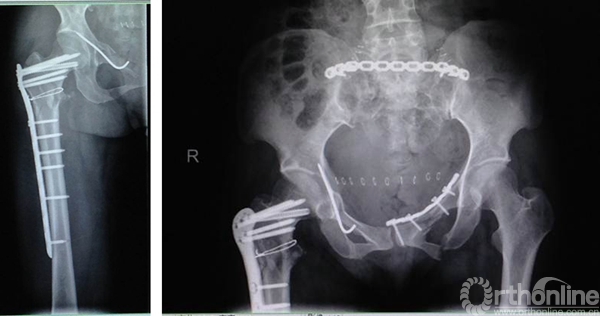

邓XX,男,56岁

术后8周